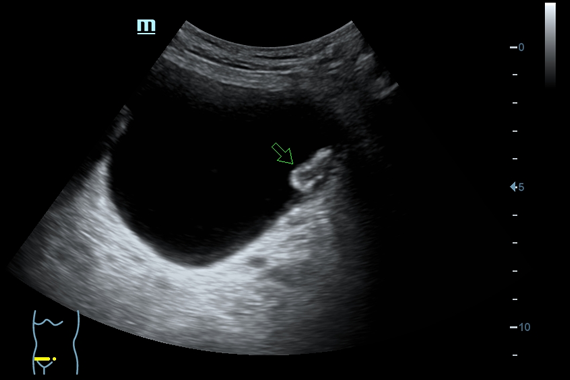

Система ультразвукового исследования Mindray DC-60 EXP X-INSIGHT является новейшей разработкой для проведения комплексных обследований на высшем уровне. Она обеспечивает решение самых сложных задач в таких областях, как кардиология, акушерство и гинекология, сосудистые заболевания, педиатрия и многие другие.

DC-60 EXP X-INSIGHT - это современный стационарный УЗИ-аппарат с функцией сенсорного управления и очищенной гармонической визуализацией, обеспечивающей лучшее контрастное разрешение и технологию 4D-визуализации. Он оснащен 21,5-дюймовым монитором, который может поворачиваться на 180 градусов, что удовлетворяет потребности врачей в качественной ультразвуковой диагностике.

• Поддержка режимов сканирования B/M/Цветовой доплер CDI/Цветной M/Энергетический доплер PD/Направленный энергетический доплер Dir.PD.